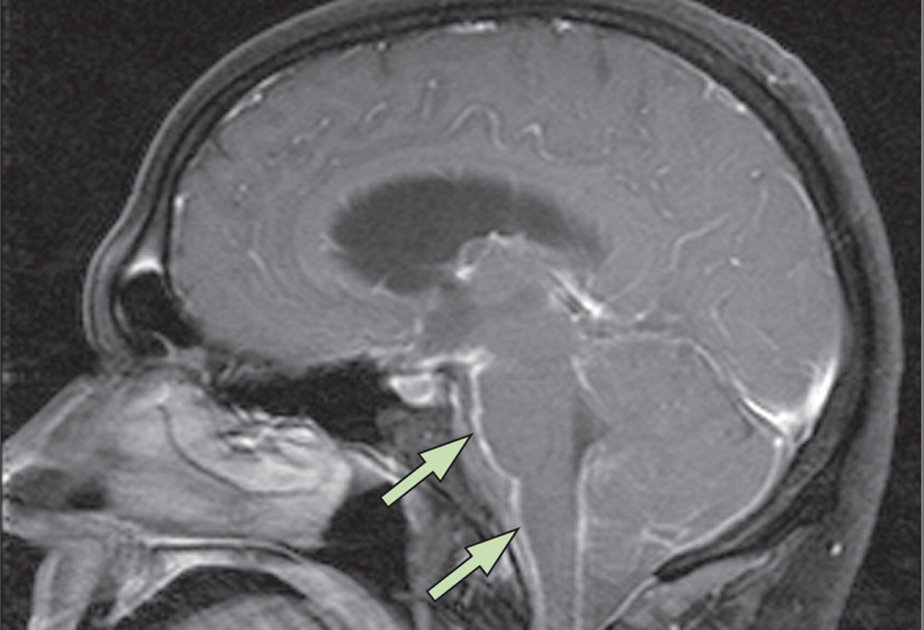

Meningococcal infections are caused by Neisseria meningitidis, a bacterium that affects the membranes of the human brain and spinal cord.